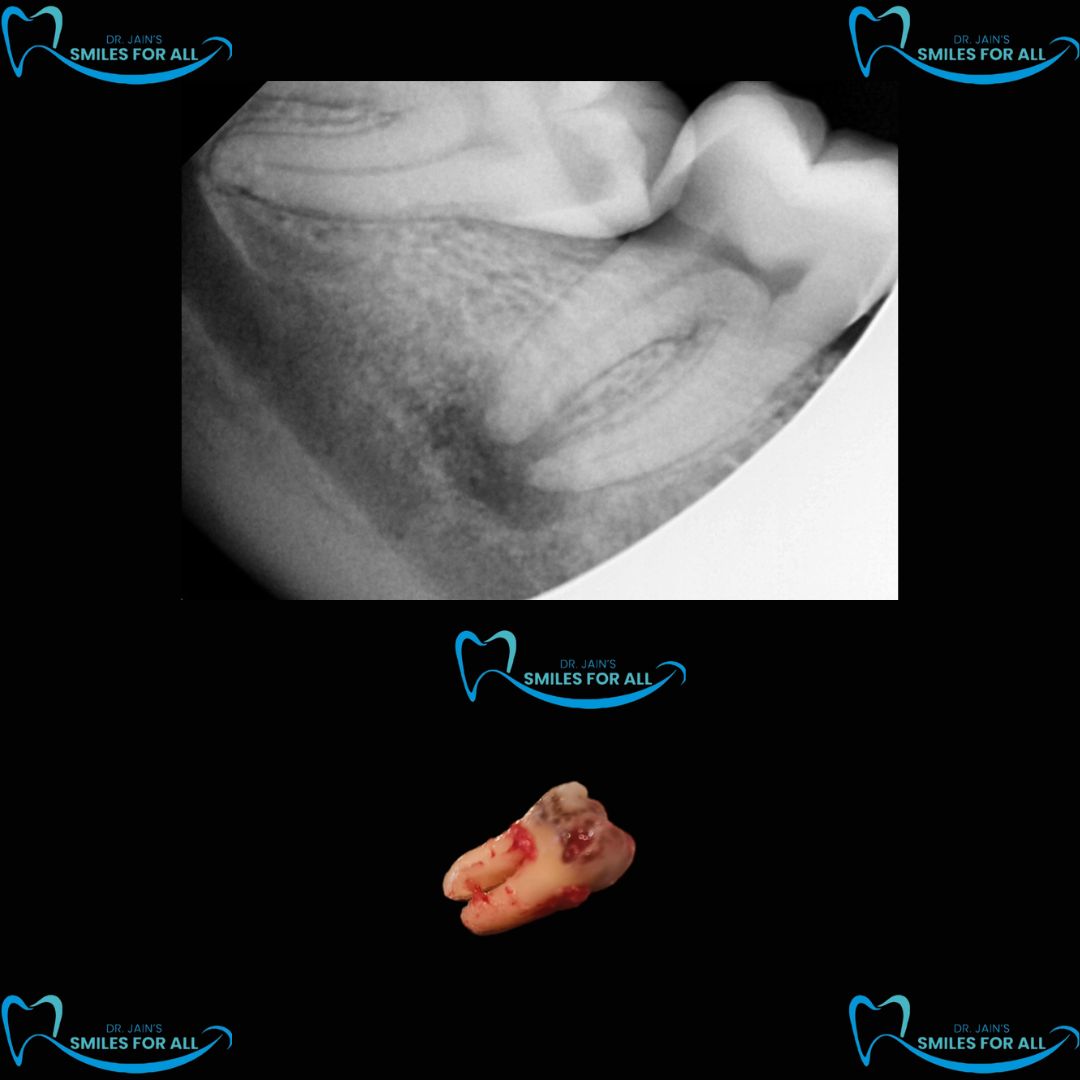

Best Dental Clinic in Rohini Sector 11 Wisdom tooth pain can be very sharp and shooting and may require urgent treatment. Visit Smiles For All Dental Clinic , The Best Dental Clinic in Rohini Sector 11 for Best Tooth Extraction services by The Best Oral Surgeon in Rohini. Contact us for more information.